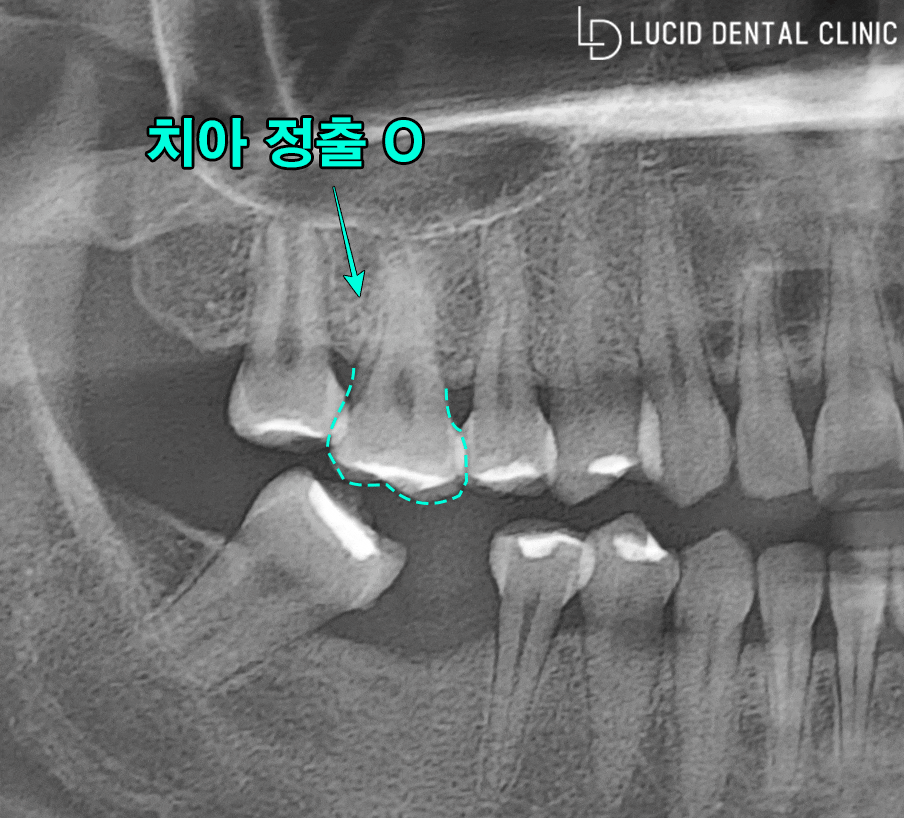

사진에 표시해 드린 것처럼

여러 문제점이 관찰되고 있는데요

- 발치 후 시간이 오래

지나면서 생긴 치조골 흡수

- 반대편 어금니 치아 정출

- 인접치아 기울어짐

이렇게 3가지로 말씀드릴 수 있겠습니다.

우리 치아들은 가만히 있는 것처럼 보여도

각자 조금씩 움직이려는 특징을 가지고 있는데요

발치 후 빠른 시간 안에

빈 자리를 채워 넣지 않으면

반대편 치아가 점점 솟구쳐 올라오고(정출)

주변 치아가 빈 자리로 기울어지는 증상이 나타나

정상 치열에서 벗어날 가능성이 있습니다.